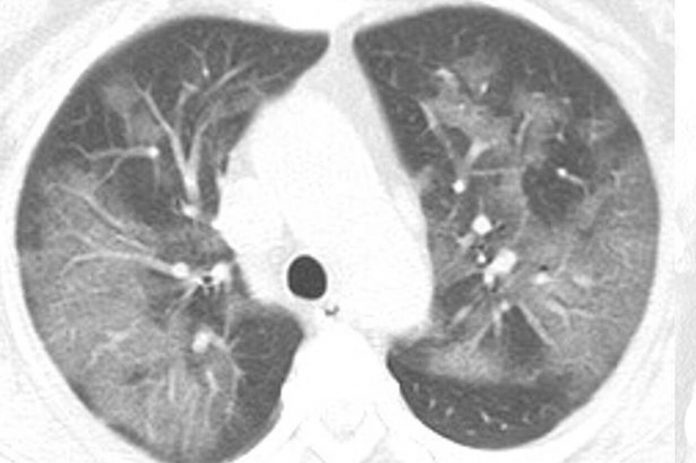

Αυτή είναι η ακτινογραφία ενός 54χρονου ασθενή στην Κίνα, ο οποίος νόσησε από τον ιό.